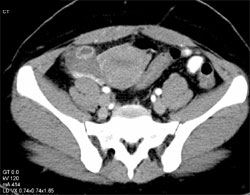

Early Pregnancy